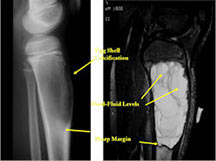

- The cystic spaces filled with hemorrhagic material leads to the presence of fluid-fluid levels on MRIs (so called ABC-like changes or telangiectatic change)

- Fluid-fluid levels secondary to cystic cavities filled with blood products. The sediment from blood products settle to the gravity dependent area of the cavity and the fluid component floats to top thus forming a fluid-fluid level.

- MRI and CT are also useful for demonstrating the local extent of the tumor and any soft tissue mass

- CT also useful for demonstrating scant osteoid production

- ABC usually has peripheral “egg shell†calcification indicating that the periosteum is intact around the soft tissue component (a benign radiographic feature)